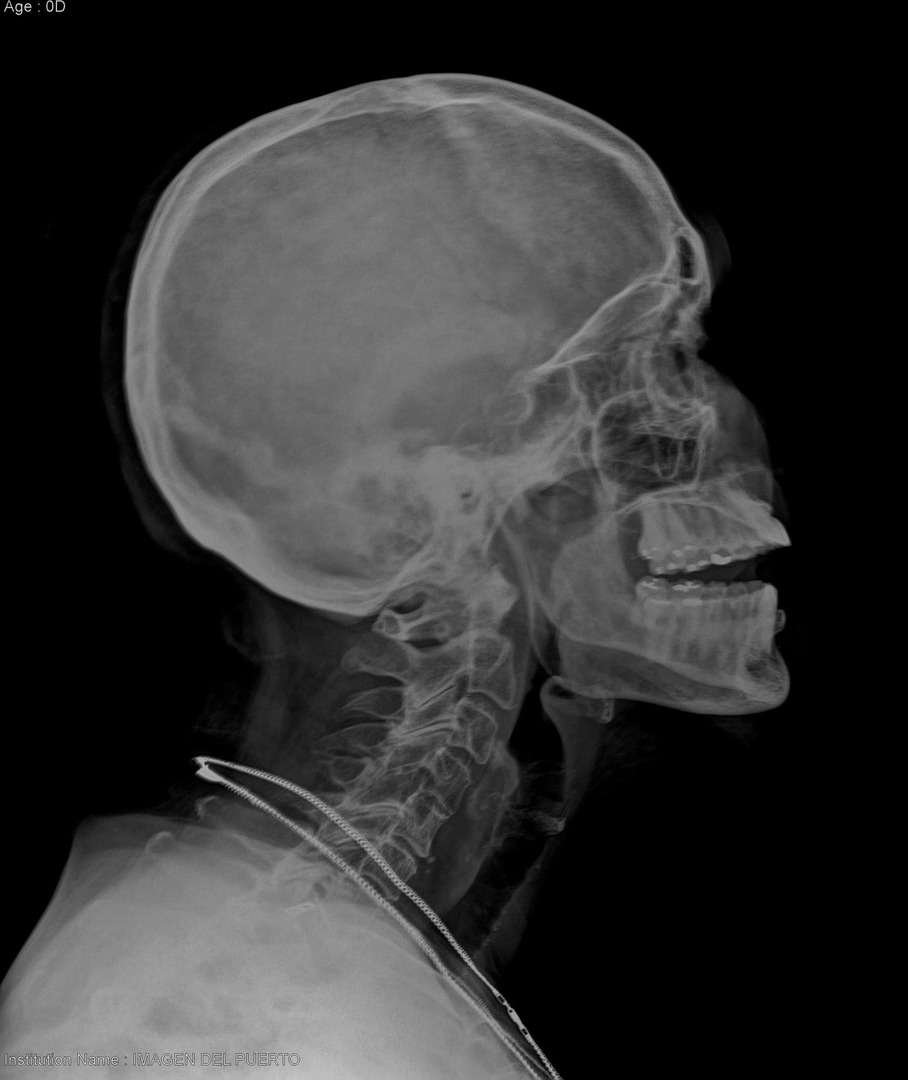

Se atiende urgencia, paciente cae sobre su propia altura, refiriendo dolor en cráneo y columna cervical.